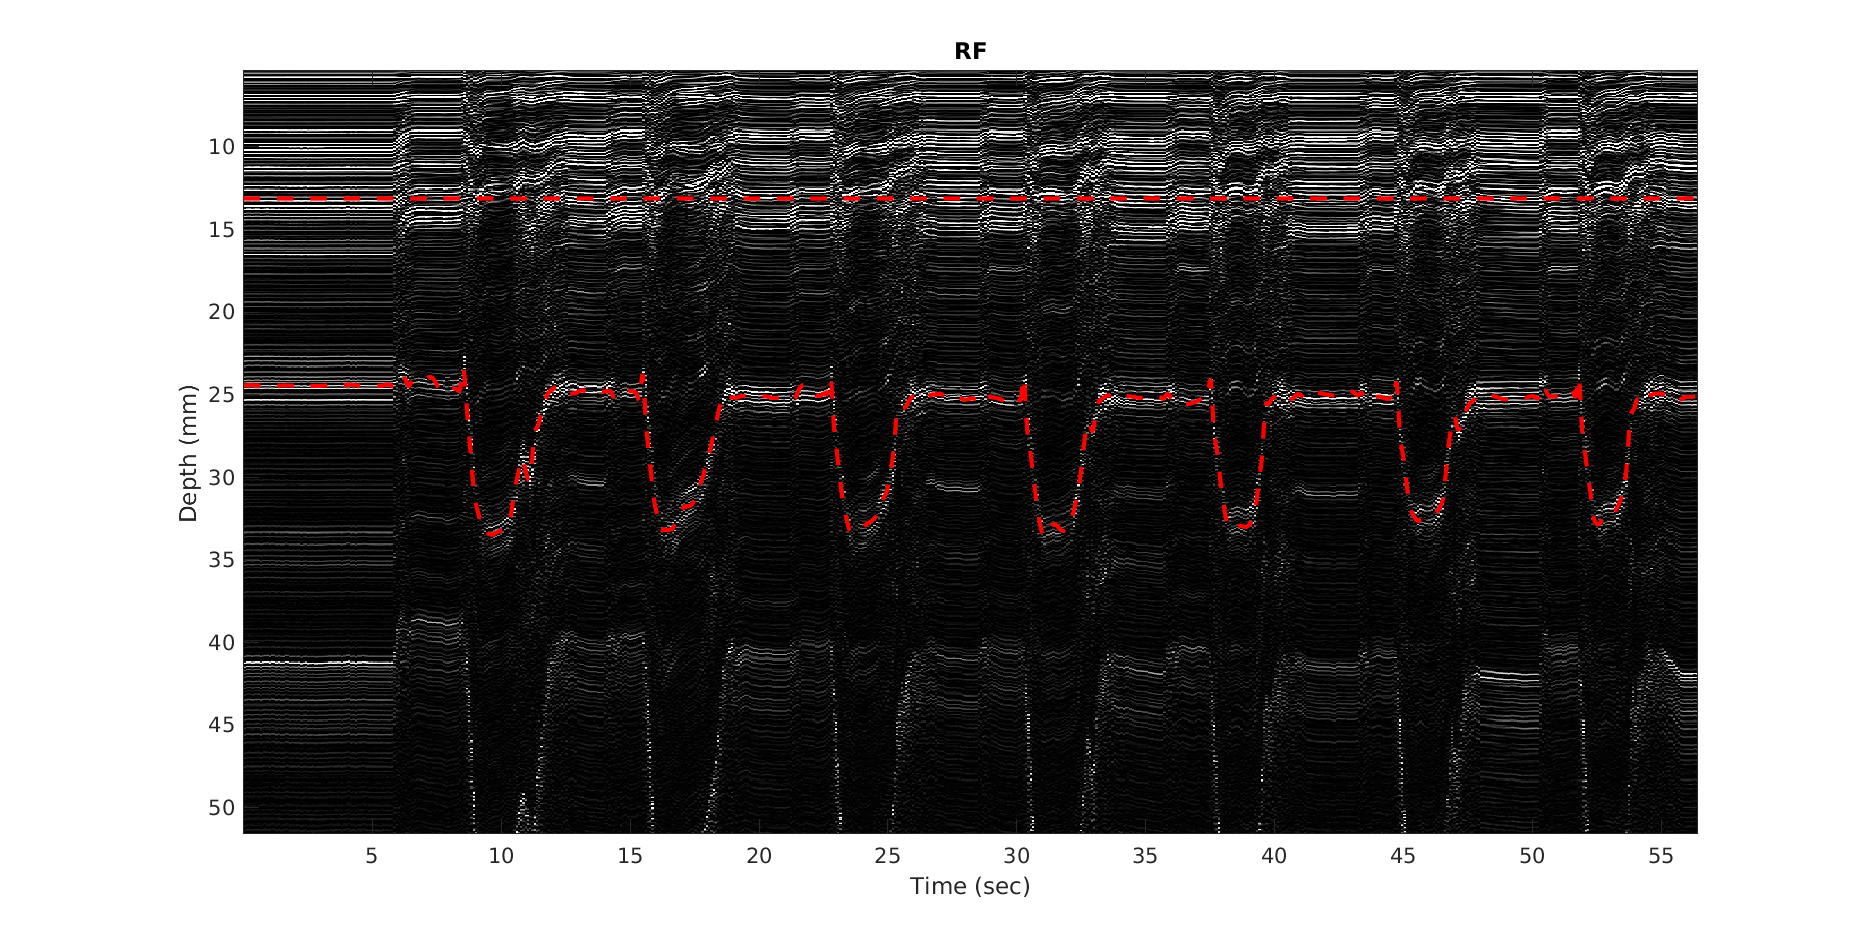

1. A模式超声技术

A模式超声技术是一种通过测量超声波在组织中传播的速度和时间来评估组织特性的方法。在本研究中,我们采用单元件超声换能器,通过连续发送超声波并接收反射信号,实时跟踪肌肉厚度的变化。

4. 动态现实任务实验

在验证了模型在受控条件下的准确性后,我们进一步将其应用于动态现实任务中,包括举重、骑自行车、跑步机运动和室外运动。通过佩戴可穿戴A模式超声设备,实时记录肌肉厚度变化,并估计关节扭矩。

2. 动态现实任务实验结果

在动态现实任务中,可穿戴A模式超声设备成功地实时记录了肌肉厚度变化,并估计了关节扭矩。尽管动态活动中的肌肉活动模式更为复杂,但我们的方法仍然能够在举重、骑自行车、跑步机运动和室外运动等任务中提供可靠的关节扭矩估计。